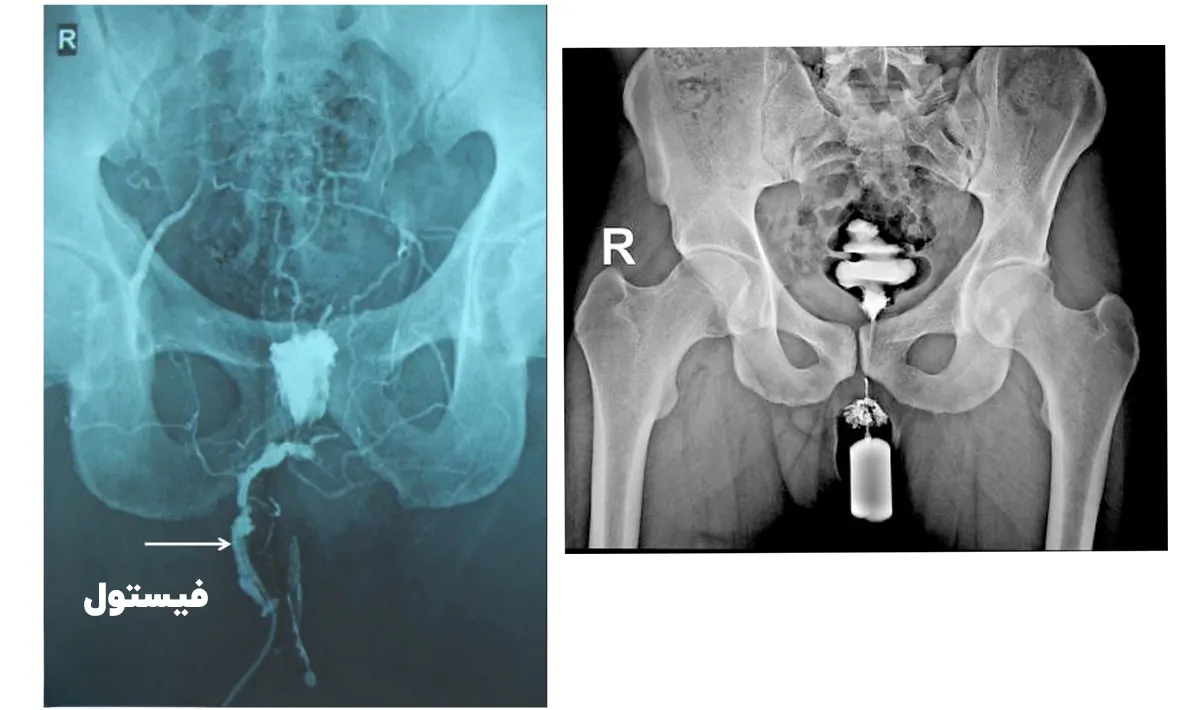

در طول فیستولوگرافی، بیمار روی تخت مخصوص تصویر برداری اشعه ایکس قرار می گیرد. سپس ناحیه اطراف فیستول با مواد ضدعفونی کننده استریل می شود. از بی حسی موضعی برای بی حس کردن ناحیه استفاده می شود تا بیمار در طول این روش حداقل درد و ناراحتی را تجربه کند.

در این مرحله یک برش کوچک در نزدیکی فیستول ایجاد شده و یک کاتتر با دقت وارد می شود. از طریق این کاتتر رنگ کنتراست یا ماده حاجب به محل تزریق می شود تا تصاویری واضح در عکس برداری قابل مشاهده باشد.

رادیولوژیست در حین عبور رنگ از فیستول، چندین مرتبه تصویر برداری انجام می دهد. این کار به شناسایی مجاری فیستول و جهت درمان بهتر آن کمک خواهد کرد. عمل فیستولوگرافی معمولاً حدود 30 تا 60 دقیقه طول می کشد.

فیستولوگرافی به کمک دستگاهی به نام فلوروسکوپی که به یک صفحه مانیتور وصل است انجام می شود و می تواند به صورت زنده و عکس تصاویر مورد نیاز را ایجاد کند.